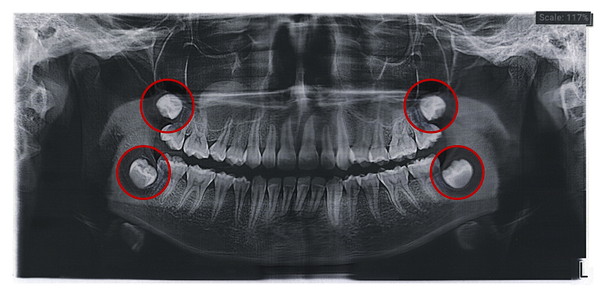

レントゲン写真を撮影すると、歯ぐきの中の状態も確認することができるため、親知らずをどのように治療するか検討できます。

親知らずの状態を確認するためにレントゲン撮影をして、親知らずの位置やほかの歯の影響を及ぼしていないか確認します。

痛みや腫れを繰り返し、ほかの歯に影響を及ぼしている場合には、抜歯が検討されます。

レントゲン撮影で血管の位置や神経の位置を確認しますが、難しい親知らずの抜歯の場合には、必要に応じてCT撮影をして立体的な画像で確認することもあります。

一般的なレントゲンは平面ですが、CTは3次元的な画像の確認ができるため、歯の根の形や顎の骨との関係も確認することができます。

CTを確認しながら、抜歯のシュミュレーションも行うことが可能です。